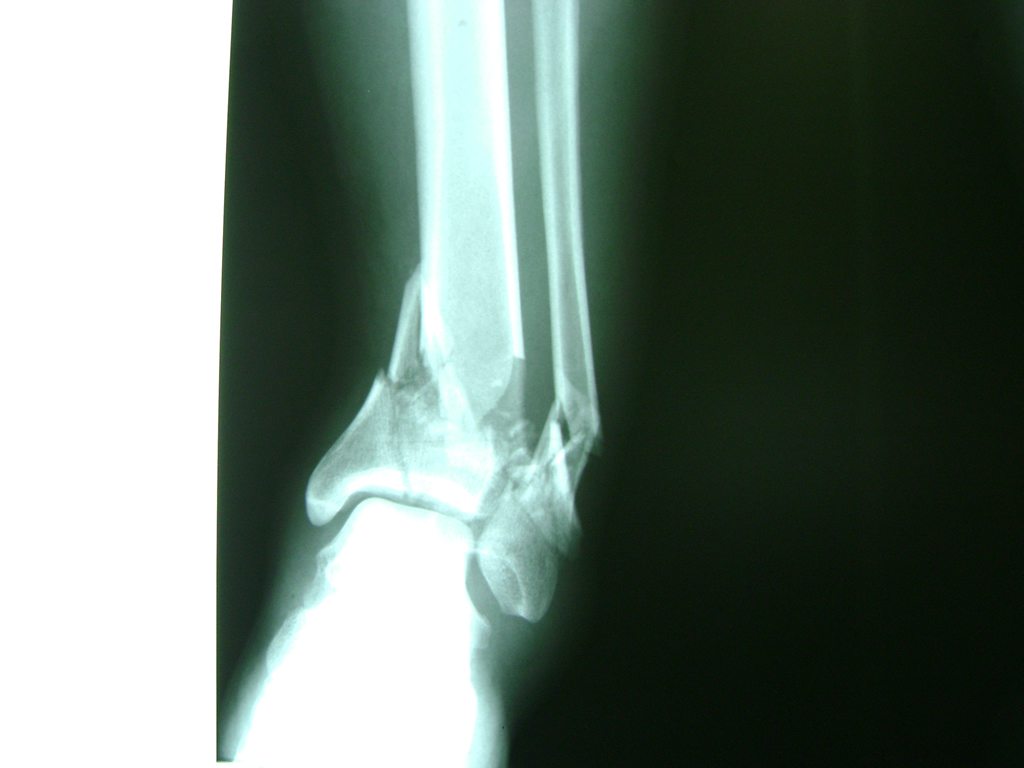

Una fractura de tobillo es la rotura de uno o más de los huesos del tobillo. Estas fracturas pueden ser:

- Los extremos de los huesos están desalineados entre sí (desplazados).

- La fractura se extiende hasta la articulación del tobillo (fractura intra-articular).

- Los tendones o ligamentos (tejidos que sujetan los músculos y los huesos entre sí) están rotos.